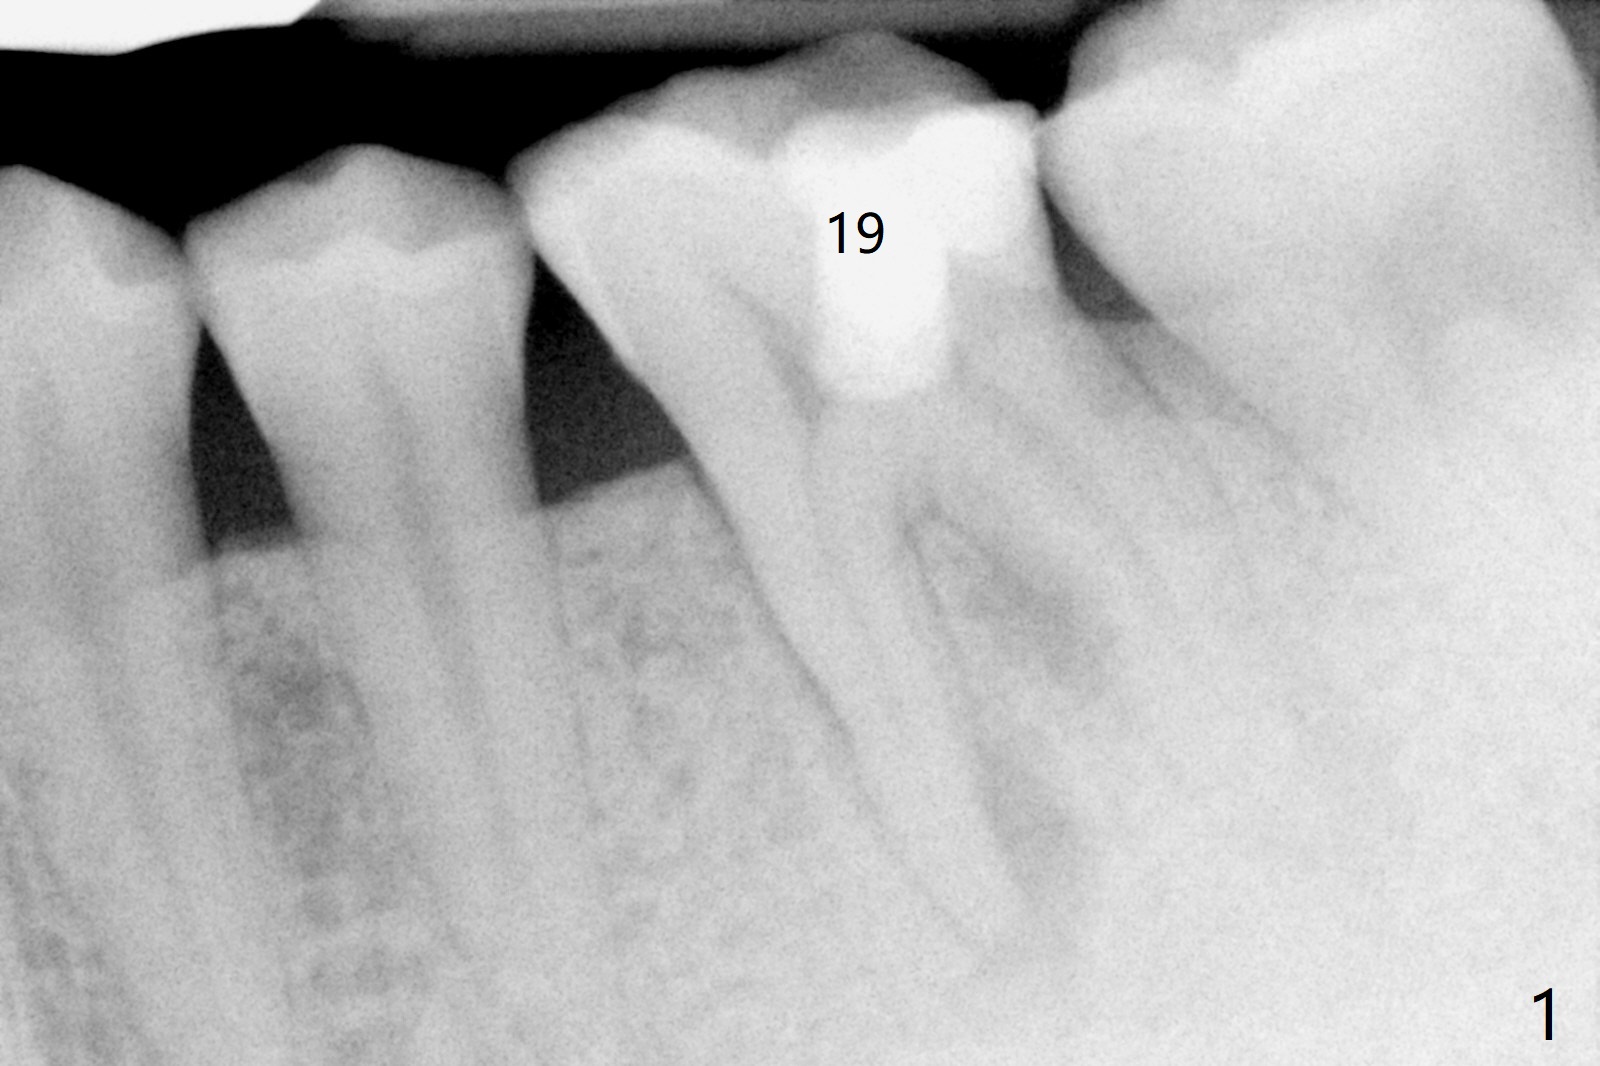

A 29-year-old man has chronic apical perio-dontitis at #19 (Fig.1) for 5 years before RCT with apical buccal swelling (Fig.2). Three days post RCT a fistula develops (Fig.3); curettage is performed. Crown is prepared 3.5 years later (Fig.4). Bitewing is taken immediately before cementation (Fig.5). There is no leakage 2 years 8 months post cementation (Fig.6,7) or periapical radiolucency 6 years 3 months post RCT (Fig.8). Return to Professionals Xin Wei, DDS, PhD, MS 1st edition 11/27/2019, last revision 11/28/2019